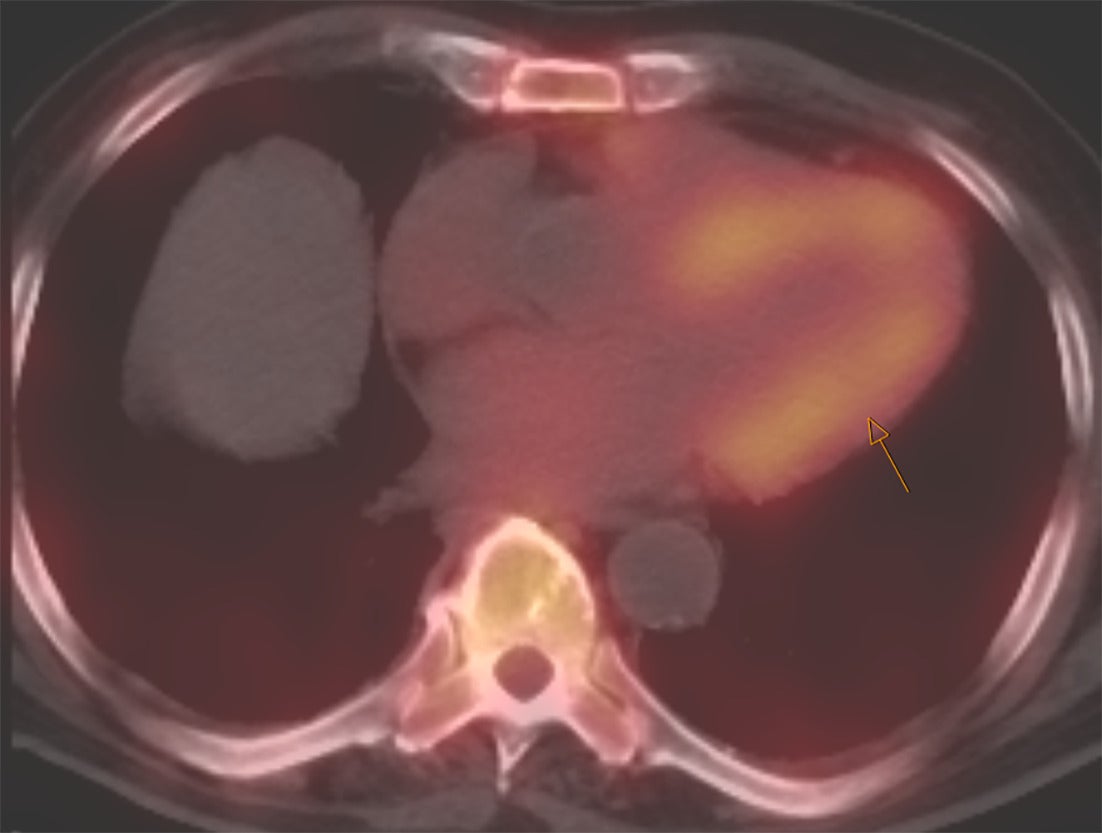

Perugini et al. in 2005 demonstrated that 99mTc-DPD (diphosphono-1,2-propanodicarboxylic acid) scintigraphy could noninvasively differentiate ATTR cardiac amyloidosis from AL amyloidosis with high accuracy.12 ATTR cardiac amyloidosis showed uptake for bone radiotracers, whereas AL cardiac amyloidosis showed minimal to no uptake ( Figures 1 , 2 ). They also developed the visual Perugini grading scale (0‐3) for semiquantitative assessment as below.12

SPECT/CT image of the chest with strong myocardial uptake (shown by arrow) consistent with TTR amyloidosis.